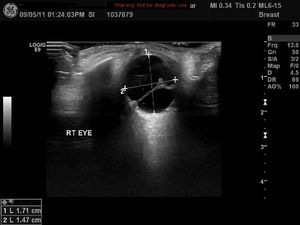

Persistent Hyperplastic Primary Vitreous (PHPV)Published: April 26th 2012 | Updated: